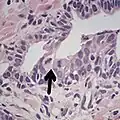

-

Intraductal carcinoma of the prostate with an infiltrative growth pattern may be morphologically difficult to distinguish from invasive cancer. One focus shows comedonecrosis (arrow), morphologically suggesting Gleason pattern 5 invasive carcinoma (a haematoxylin and eosin, b CK5/6)[20] -